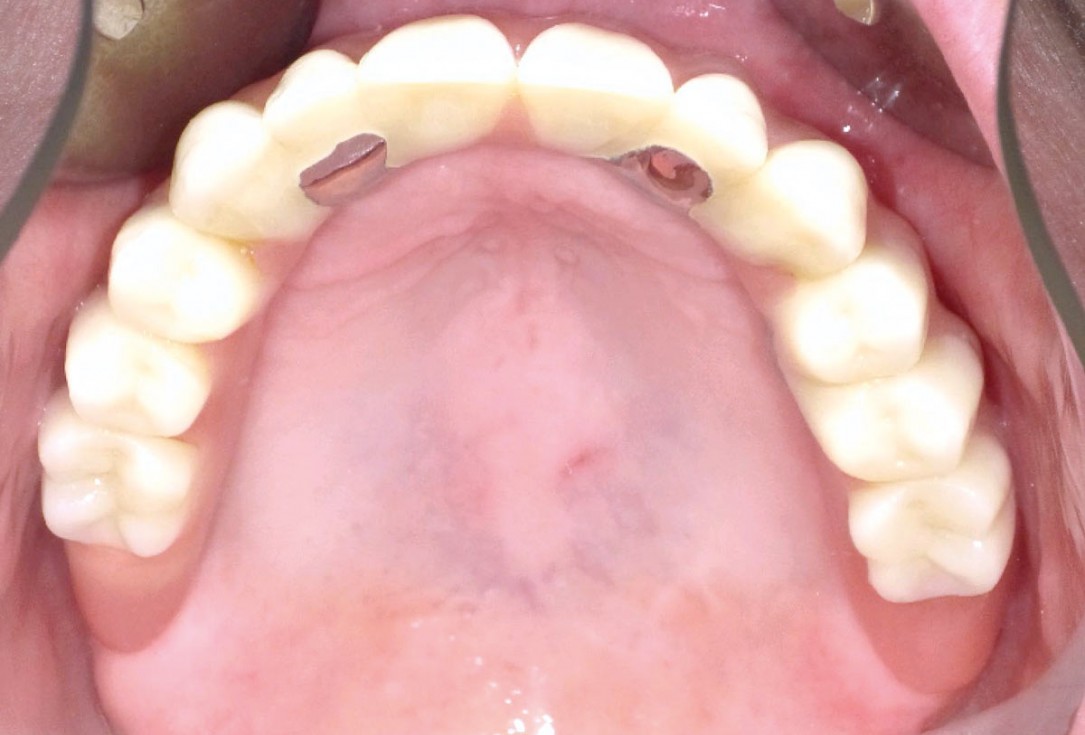

17/23 - Six months follow-up – stable situation

Full arch reconstruction of the maxilla with maxgraft® bonebuilder - Dr. M. Erbshäuser

18/23 - Six months follow-up – stable situation